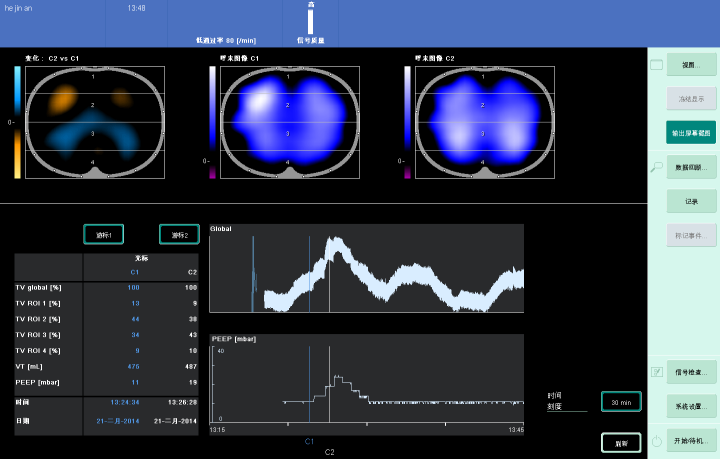

(3)EIT:可进行实时动态监测,通过肺内气体含量的改变导致电阻抗的变化。蓝色区域和白色区域是肺通气区域,黑色区域是通气不良区域,包括实变区域。

图片

EIT可以显示肺复张后通气分布的变化,下图蓝色和白色区域都显示通气良好。

从下图可以看到,肺复张后,背侧塌陷肺泡打开,通气中心从非重力依赖区向重力依赖区移动,背侧区(3+4)的通气占全部通气的比例从26%增加到51%,存在可复张性。

EIT可以显示肺复张后各区域呼气末肺容积的变化。复张的高压力会带来呼气末肺容积的增加,EIT图像中可以见到电阻基线位置上移,结合潮气量监测值,即可通过EIT计算各区域的呼气末肺容积变化值。高复张性患者重力依赖区呼气末肺容积的增加比例要高于低复张性患者,说明高复张性下重力依赖区的呼气末肺容积明显增加。低复张性患者,呼气末肺容积的增加则更多集中在腹侧,有过度膨胀的风险。

研究发现,EIT可以评价肺的可复张性,随着PEEP的升高,全肺通气得到改善,重力依赖区通气明显增加,与CT的变化基本一致。